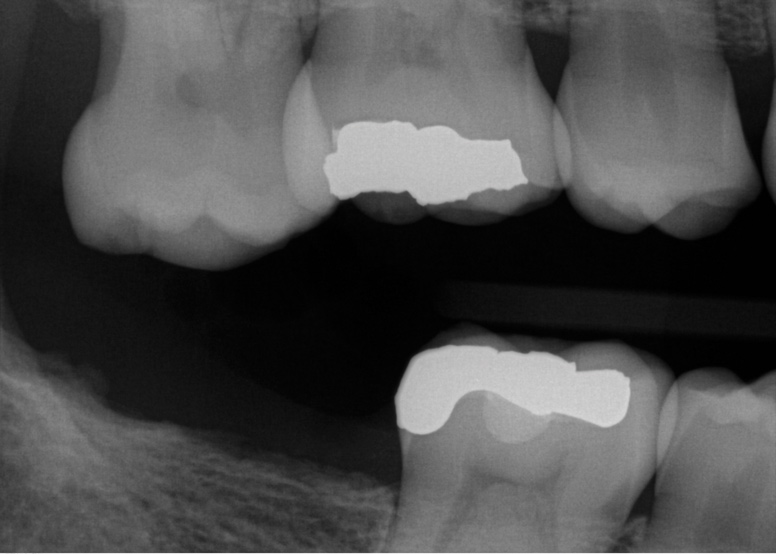

Fig 3. Patient No. 1, contralateral side; in 2009 patient presented with teeth Nos. 15 and 18. Subsequently, tooth No. 18 was extracted due to tooth fracture.

Figure 3

Fig 4. Patient No. 1 in 2016, with extrusion of tooth No. 15. Two different experiences in the same mouth, as shown in Figs 1–2 and Figs 3–4, underscore the unpredictability of extrusion.

Figure 4